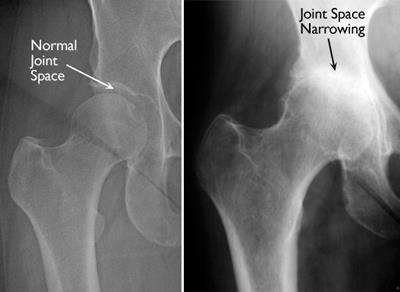

Moderate joint space narrowing small subchondral cysts of the femoral head andor acetabulum moderate loss of sphericity of the femoral head. Arthrosis of the hip joint ie. EVERY morning before you get out of bed.

An effusion is fluid. If you have Stage 3 osteoarthritis of the hip youre not only experiencing pain and stiffness when you first get moving. Severe joint space narrowing or obliteration large subchondral cysts severe deformity of the femoral head.

No labral irregularity is not a tear. The gap between the bones narrows as the joints become inflamed and collagen fragments are released into the synovial fluid that lubricates the joints. Bone tissue grows osteophytes bone protrusions which cause pain.